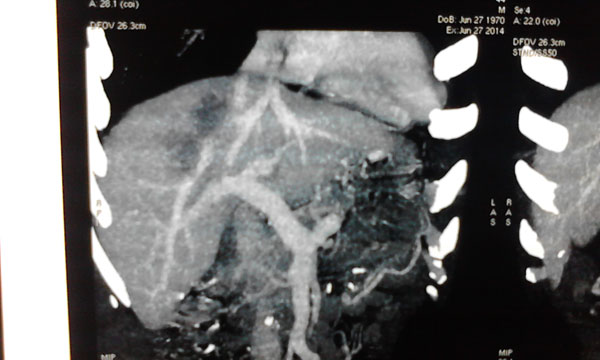

肿瘤与肝动脉

肿瘤与肝静脉